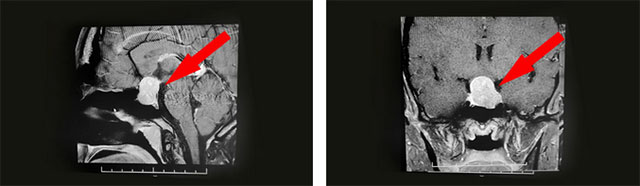

经过医院仔细检查发现:鞍区MRI平扫+增强显示:蝶鞍扩大,鞍底骨质下陷;鞍内垂体可见类椭圆形异常信号,大小约2.5*1.6cm,垂体柄未见明显显示;鞍上结构尚清,视交叉上抬;病灶与双侧海绵窦分界清晰;所示蝶窦局部黏膜增厚。

▲ 影像检查显示:垂体大腺瘤,超蝶鞍生长